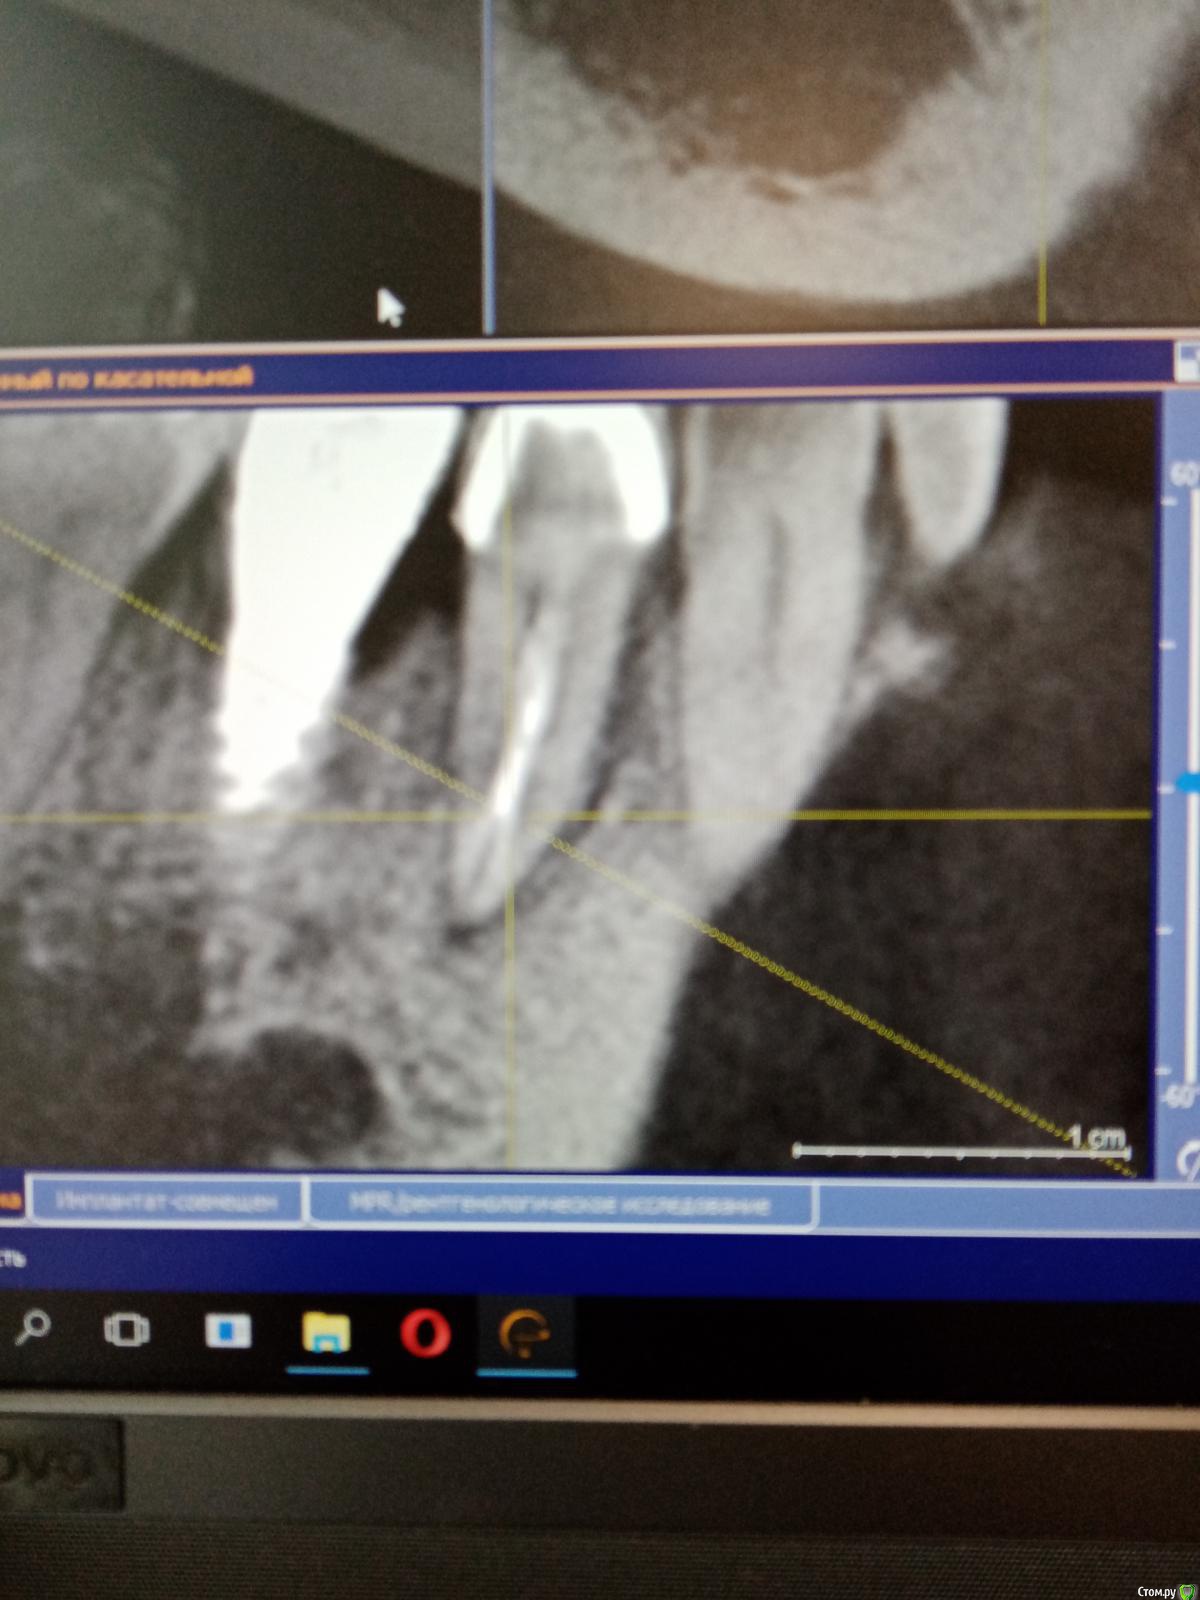

Raimar Опубликовано 30 июня, 2020 Поделиться Опубликовано 30 июня, 2020 (изменено) Зуб 4.5, ранее лечен, (эндо), пациентка пришла ко мне на перелечивание с острой болью, основную гуттаперча удалил,далее файл упирается, нужно ли пытаться распломбировать маленькие канальцы? Изменено 30 июня, 2020 пользователем Raimar Ссылка на комментарий

vse32 Опубликовано 1 июля, 2020 Поделиться Опубликовано 1 июля, 2020 Не, кт уже вижу. По-хорошему прямо надо каналы пройти. Ссылка на комментарий